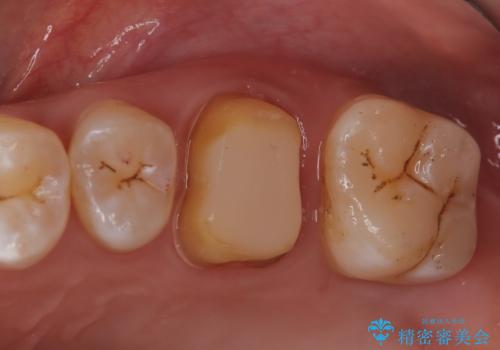

【見逃し根管を発見】根管治療〜セラミッククラウン

- 他院で根管治療した歯の再治療を希望されて来院されました。

未処置の根管があったため、マイクロスコープにて観察したことで、見逃しの根管を含めて清掃・充填を行うことができました。

上顎第一大臼歯は基本的に4根管です。